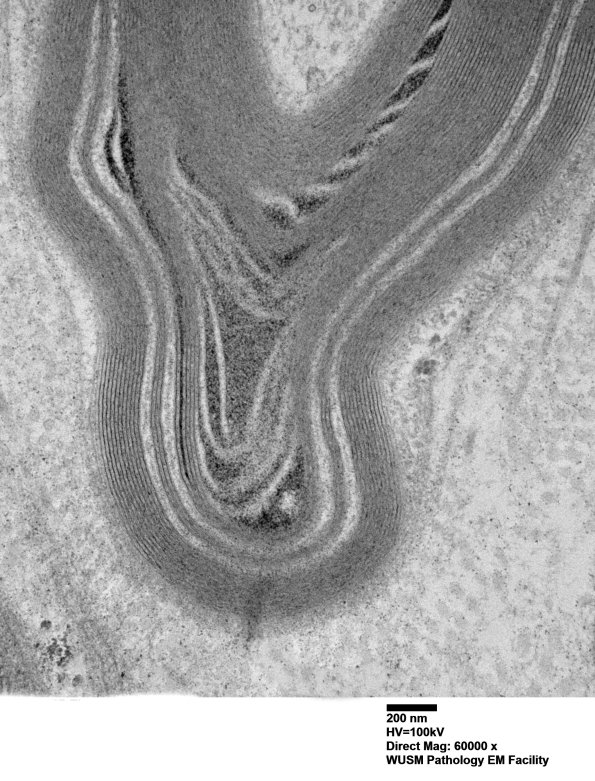

In this case there is an association of WSM and a Schmidt-Lanterman cleft. (electron micrographs)